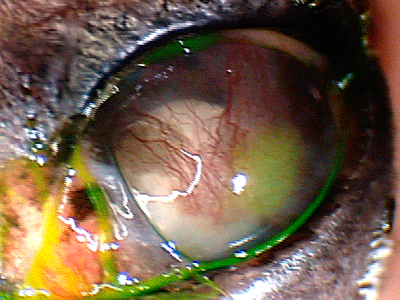

Cataract complications – Chronic presence of cataract in this patient resulted in chronic inflammation, glaucoma, development of corneal ulcer and ultimate need for the surgical eye removal.

Cataract complications – Chronic presence of cataract in this patient resulted in chronic inflammation, glaucoma, development of corneal ulcer and ultimate need for the surgical eye removal.